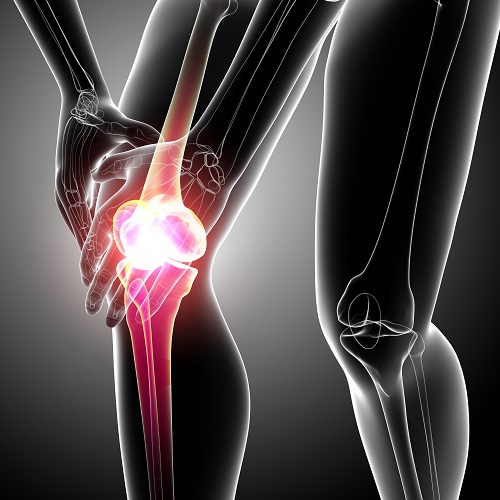

뼈랑 뼈 사이에는 연골이 있어요. 연골이 망가진다는 소리는 뼈랑 뼈가 바로 닫게 된다는 소리 이라고 합니다. 그러면 통증이 발생하게 되죠. 무릎을 움직일 때 마다 통증이 생기고 불편해져요. 무릎 운동이 뻐근해지고 힘들어져요.

격렬한 스포츠 운동을 하다가 부상을 당하는 경우 무릎에서 뻑! 하고 강력한 소리가 들립니다. 이 소리는 연골이 찢어지거나 인대가 파열되는 소리 이라고 합니다. 초기에는 별 통증이 없을 수 있어요. 더욱 심해지거나 운동하는데 어려움이 발생하게 돼요.